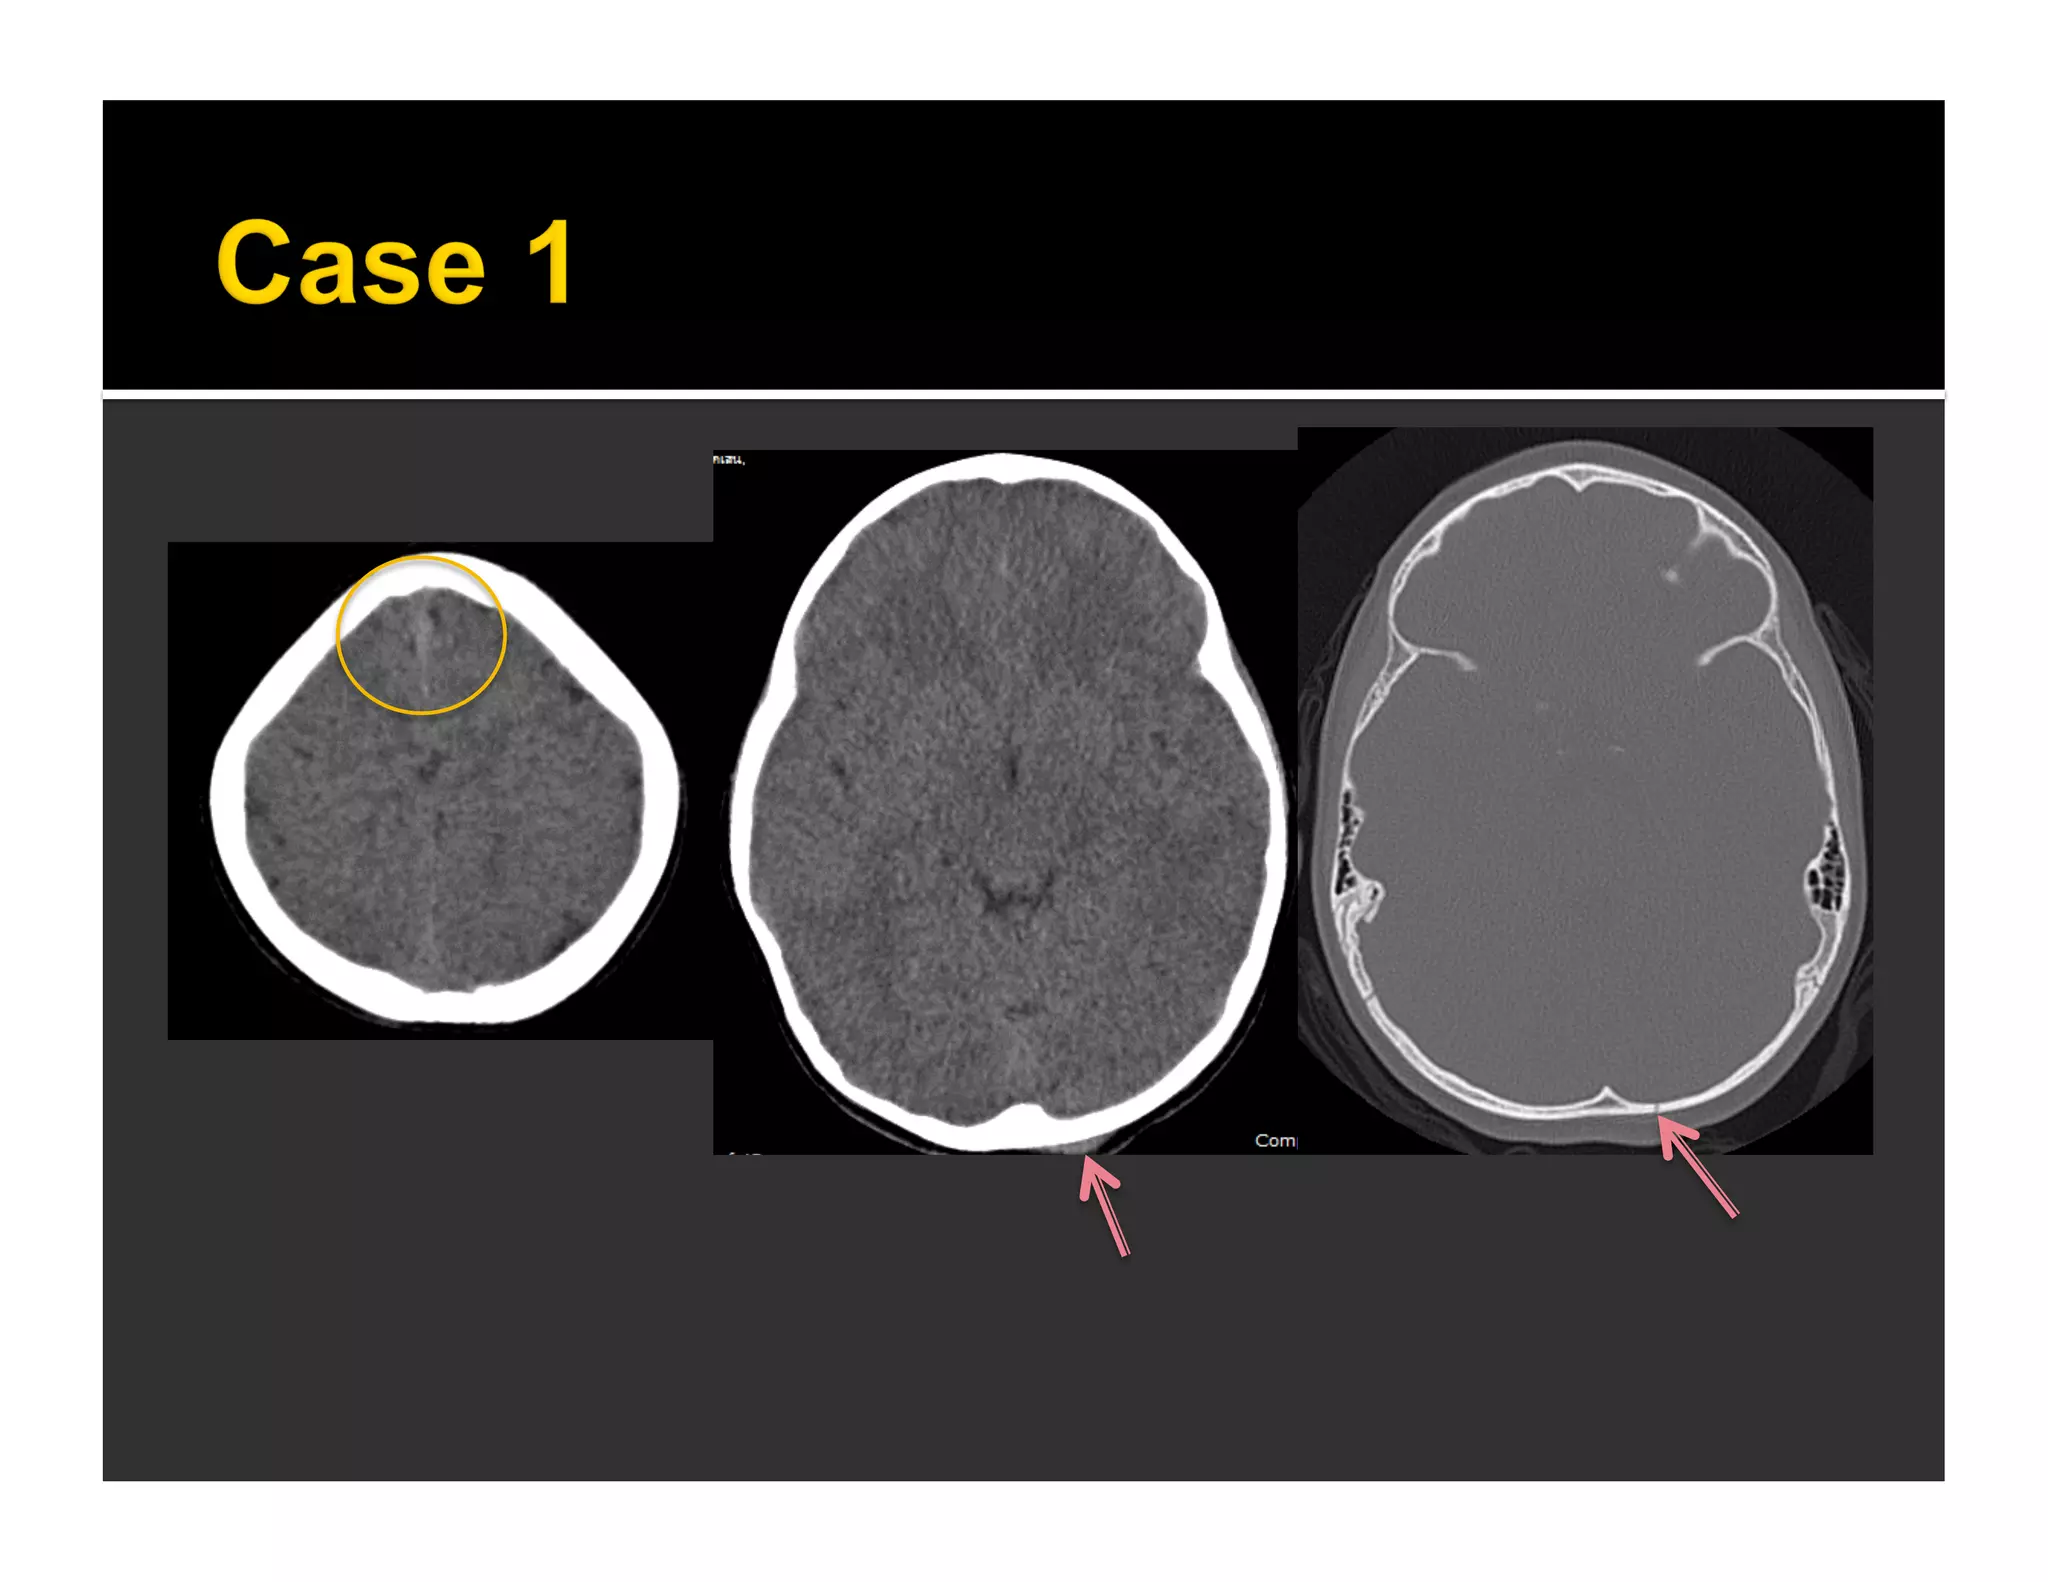

 213 NCCTs

▪ 32 cases with traumatic ICH = 104 foci on either

axial or coronal images

▪ 80 foci were true-positive lesions

▪ 15 true positives not detected on axial images

(15/104 = 14%, in 8 patients)

▪ 14 false-positive findings on axial but excluded on

coronal

 Axial images are less accurate in areas

 Parallel to axial image plane (esp immediately

adjacent to bony surfaces)

 Common areas where false negatives occur

 Floor of anterior cranial fossa

 Floor of middle cranial fossa

 Vertically oriented lesion easier to detect

on coronal reformation than axials

 Horizontal skull fracture

 Enable us to be certain about diagnosis

 Lesion detection

 Floor of anterior and middle cranial fossae

 Tentorial lesions

 Horizontal skull fracture

 Vertically oriented lesions